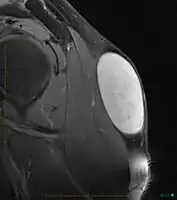

In terms of the diagnosis of a sebaceous cyst an MRI (Magnetic resonance image) may be used